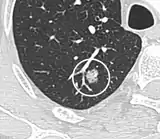

A "notch sign".[9]

A triangular perifissural node can be diagnosed as a benign lymph node.[9]